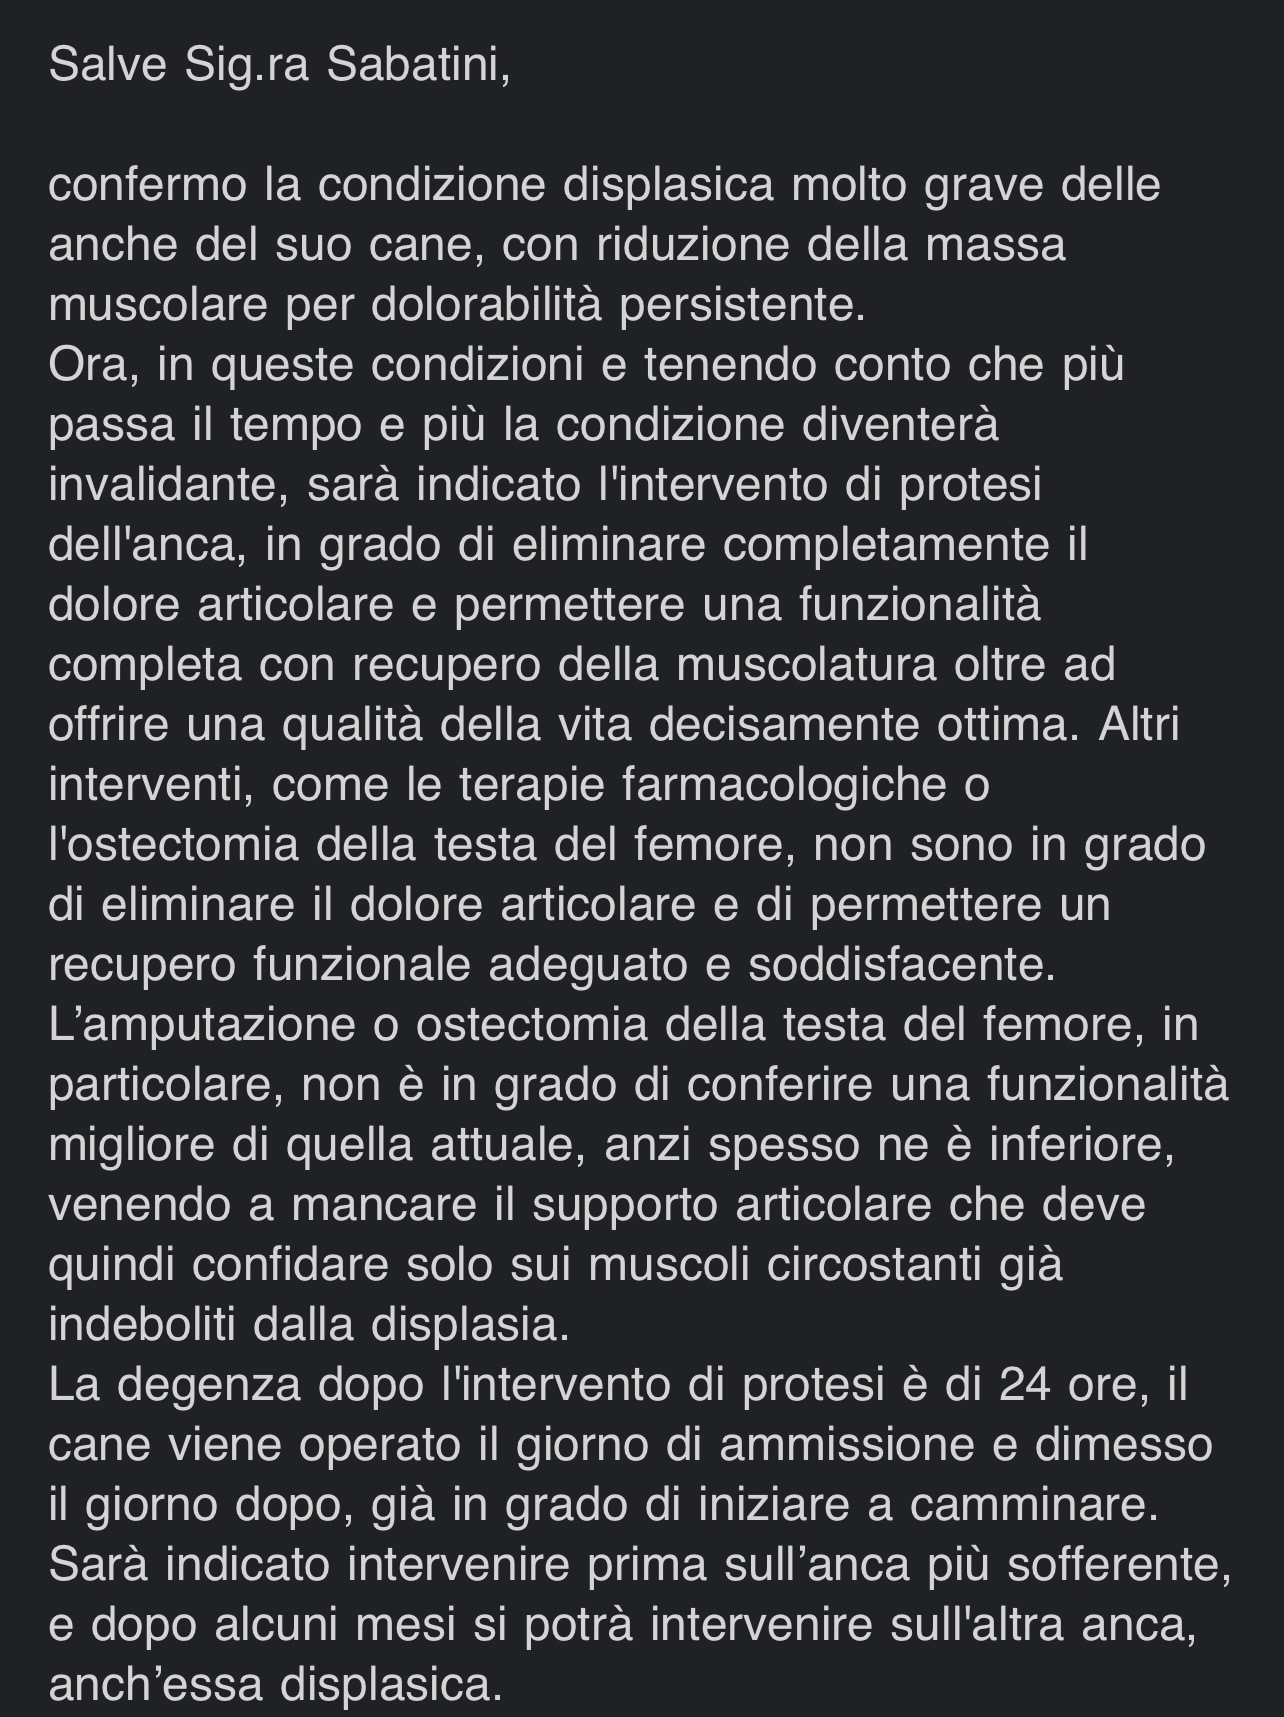

Diana ha una gravissima displasia delle anche e presto non riuscirà più a camminare. La testa del femore dell'anca sinistra è già fratturata.

Dovrà sostenere due interventi di protesi delle anche che le permetteranno di guarire al e di tornare a vivere senza dolore, correre e giocare.

Diana sarà operata nella clinica di Cremona dal professore Vezzoni il 12 giugno alla prima anca.

Dopo circa un mese si interverrà sulla seconda anca.

Vi allego le lastre delle anche di Diana e la risposta del professore Vezzoni.